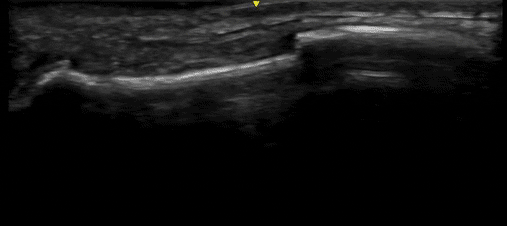

Case 3

Here we see a 17-year-old football player with a shoulder injury. Again, we had the answer before we left the bedside as the displaced fracture is clear on the ultrasound.